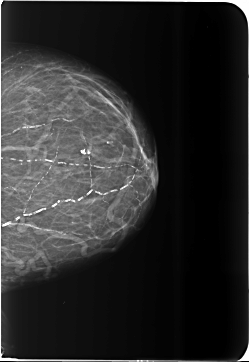

B_3481_1.LEFT_CC

LEFT_CC LINES 5784 PIXELS_PER_LINE 3984 BITS_PER_PIXEL 12 RESOLUTION 50 NON_OVERLAY